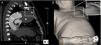

After two years, the patient caught influenza with intense cough and suddenly noticed a pulsatile lump in his left chest wall. A new CT revealed the aneurysm expanding through the first left intercostal space, reaching the chest wall surface (Figure 2).

Figure 2.

Pulsatile mass in the left chest wall noticed by the patient (B, with detail in box) and corresponding sagittal CT image (A) showing a giant aneurysm (*) measuring 70 mm×75 mm×95 mm expanding through the first left intercostal space (box).